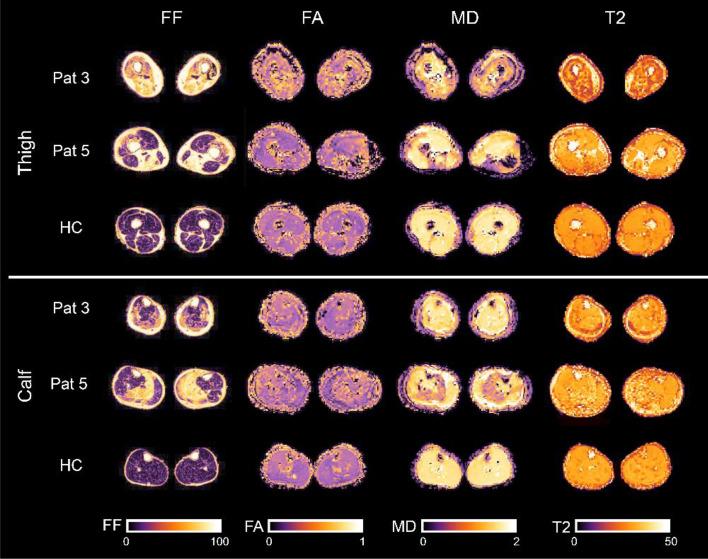

To evaluate differences in qMRI parameters of muscle diffusion tensor imaging (mDTI), fat-fraction (FF) and water T2 time in leg muscles of calpainopathy patients (LGMD R1/D4) compared to healthy controls, to correlate those findings to clinical parameters and to evaluate if qMRI parameters show muscle degeneration in not-yet fatty infiltrated muscles. We evaluated eight thigh and seven calf muscles of 19 calpainopathy patients and 19 healthy matched controls. MRI scans were performed on a 3T MRI including a mDTI, T2 mapping and mDixonquant sequence. Clinical assessment was done with manual muscle testing, patient questionnaires (ACTIVLIM, NSS) as well as gait analysis. Average FF was significantly different in all muscles compared to controls (p < 0.001). In muscles with less than 8% FF a significant increase of FA (p < 0.005) and decrease of RD (p < 0.004) was found in high-risk muscles of calpainopathy patients. Water T2 times were increased within the low- and intermediate-risk muscles (p ≤ 0.045) but not in high-risk muscles (p = 0.062). Clinical assessments correlated significantly with qMRI values: QMFM vs. FF: r = - 0.881, p < 0.001; QMFM versus FA: r = - 0.747, p < 0.001; QMFM versus MD: r = 0.942, p < 0.001. A good correlation of FF and diffusion metrics to clinical assessments was found. Diffusion metrics and T2 values are promising candidates to serve as sensitive early and non-invasive methods to capture early muscle degeneration in non-fat-infiltrated muscles in calpainopathies.

为了评估钙蛋白酶病患者(LGMD R1/D4)腿部肌肉的磁共振扩散张量成像(mDTI)、脂肪分数(FF)和水 T2 时间的 qMRI 参数与健康对照组之间的差异,将这些发现与临床参数相关联,并评估 qMRI 参数是否显示尚未脂肪浸润的肌肉中的肌肉退化。我们评估了 19 名钙蛋白酶病患者和 19 名健康匹配对照者的 8 条大腿肌肉和 7 条小腿肌肉。MRI 扫描在 3T MRI 上进行,包括 mDTI、T2 映射和 mDixonquant 序列。临床评估采用徒手肌肉测试、患者问卷(ACTIVLIM、NSS)和步态分析进行。与对照组相比,所有肌肉的平均 FF 均有显著差异(p<0.001)。在 FF 低于 8%的肌肉中,钙蛋白酶病患者高危肌肉的 FA 显著增加(p<0.005),RD 显著降低(p<0.004)。低风险和中风险肌肉的水 T2 时间增加(p≤0.045),但高风险肌肉的水 T2 时间没有增加(p=0.062)。临床评估与 qMRI 值显著相关:QMFM 与 FF:r=-0.881,p<0.001;QMFM 与 FA:r=-0.747,p<0.001;QMFM 与 MD:r=0.942,p<0.001。FF 和扩散指标与临床评估之间存在良好的相关性。扩散指标和 T2 值是有前途的候选物,可作为敏感的早期非侵入性方法,用于捕获钙蛋白酶病中非脂肪浸润肌肉中的早期肌肉退化。